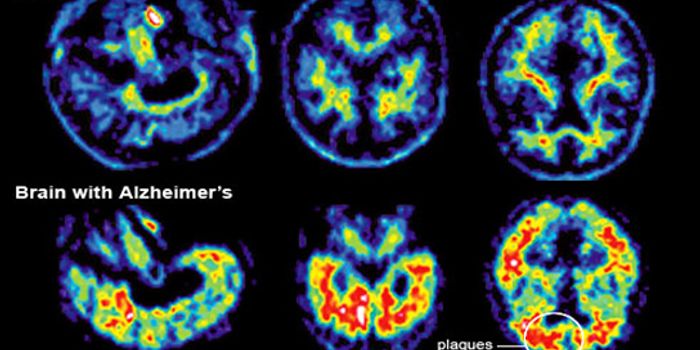

JUN 16, 2016NeuroscienceAlzheimer’s disease (AD) currently affects 5.5 million people in the U.S. over the age of 65, and that number will ...

JUN 08, 2016NeuroscienceIt’s been known for a while that plaques of the protein amyloid beta are part of the pathology of Alzheimer’ ...

MAY 11, 2016ImmunologyThe brain’s immune system potentially could be harnessed to help clear amyloid plaques, which are a hallmark of Al ...

APR 05, 2016NeuroscienceAlzheimer’s Disease (AD) is the most common form of dementia, currently affecting 5.5 million people in the U.S. T ...